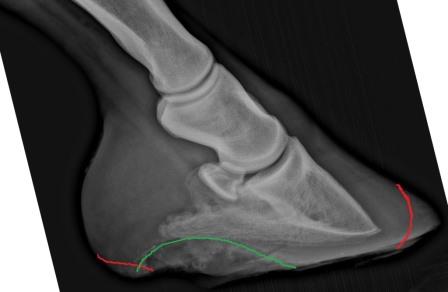

Thank you Dr. Ogelsby, I will print the article and discuss with my farrier and vet. I have attached a trimming game plan one farrier has for this horse. I know you haven't seen the horse, I understand the attempt at trimming to realign but the farrier also mentioned possible casting which I am not familiar with. In the attached pictures the farrier rotated them to show where they think the coffin bone has to be in order for the entire scenario to start healing. The red lines mark

what has to still come off, the green lines mark either thrush or high bars. If the hoof capsule needs it, the farrier will put a cast on, maybe with a sole pad, so that the hoof capsule does not abrade when he is moving around and he will get some stability and comfort. Once the coffin bone inside the hoof capsule is set ground parallel, the wall can grow again where it belongs and the laminar attachment can regenerate.

Do you have any articles on casting or an opinion?left frontright front

Because of the complications of the cast itself (primarily pressure sores), I avoid casting whenever possible even if there is some indication. I don't see the indication for it here so be sure you ask the vet what benefit is expected and be sure it makes sense.